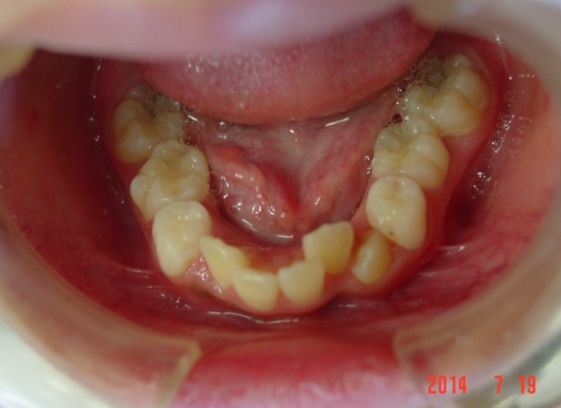

矯正前

| 症状 | 上顎前突 |

| 処置内容 | バイトブロック・プレート拡大処置・クリアアライナー・マルチブラケット装置・プレート拡大付き切歯斜面板・SHA・ディスタライザー・インビザライン |

| デメリット・院長コメント | 永久歯を抜かない治療のデメリットは、治療期間が長いことです。 ただし、その後の人生の長さを考えると、健全な小臼歯を2本または4本抜歯の矯正治療よりも、はるかにメリットがあるといえます。 また、アーチが小さくならないので、舌が後ろに押し込まれないためいびき防止につながり睡眠の質の向上にもつながります。 |